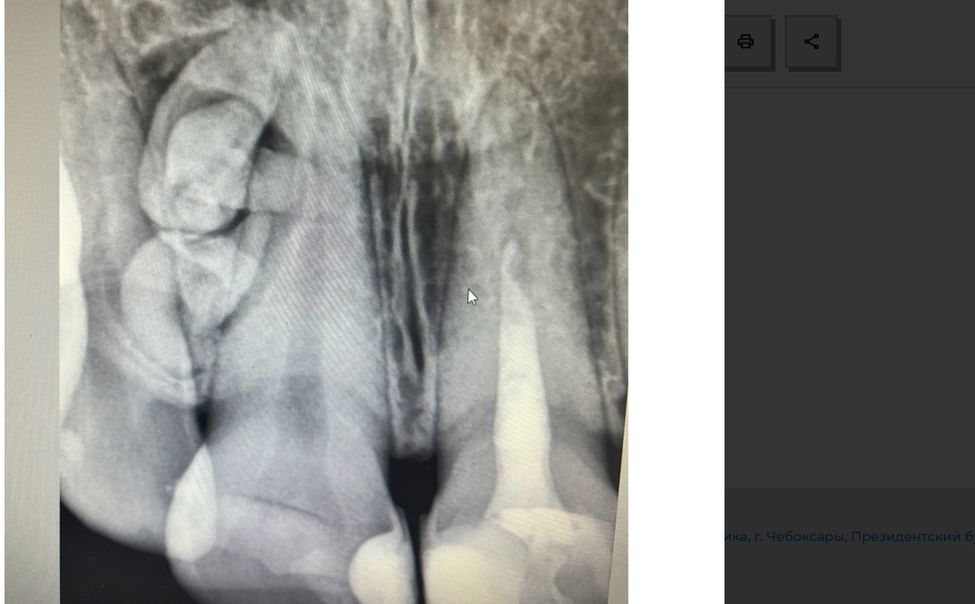

О том, что в ротовой полости «что-то лишнее», жительница Чебоксар не подозревала, пока не сделала рентген-снимок перед лечением зуба.

В панике девушка обратилась за помощью в отделение хирургической стоматологии Республиканской стоматологической поликлиники Минздрава Чувашии. Диагностирована одонтома - доброкачественное образование из зубных тканей. Выполнено хирургическое удаление новообразования.

-Операция проведена под местной анестезией,- заверил Александр Артемьев, челюстно-лицевой стоматолог-хирург Республиканской стоматологии. Ложе одонтомы обработано, рана ушита.